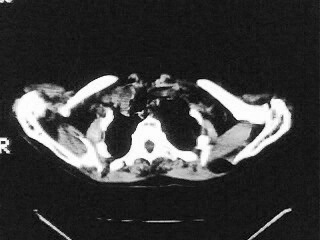

女,79,咳 嗽月余,无其它不适

1)两肺炎症。2)食管裂孔疝可能;建议行上消化道钡餐检查。

后纵隔内左心房至肝左叶后方椎体中线偏左巨大软组织包块,其壁均匀比较薄,其内可见宽气液平。

考虑食管裂孔疝。建议钡餐检查